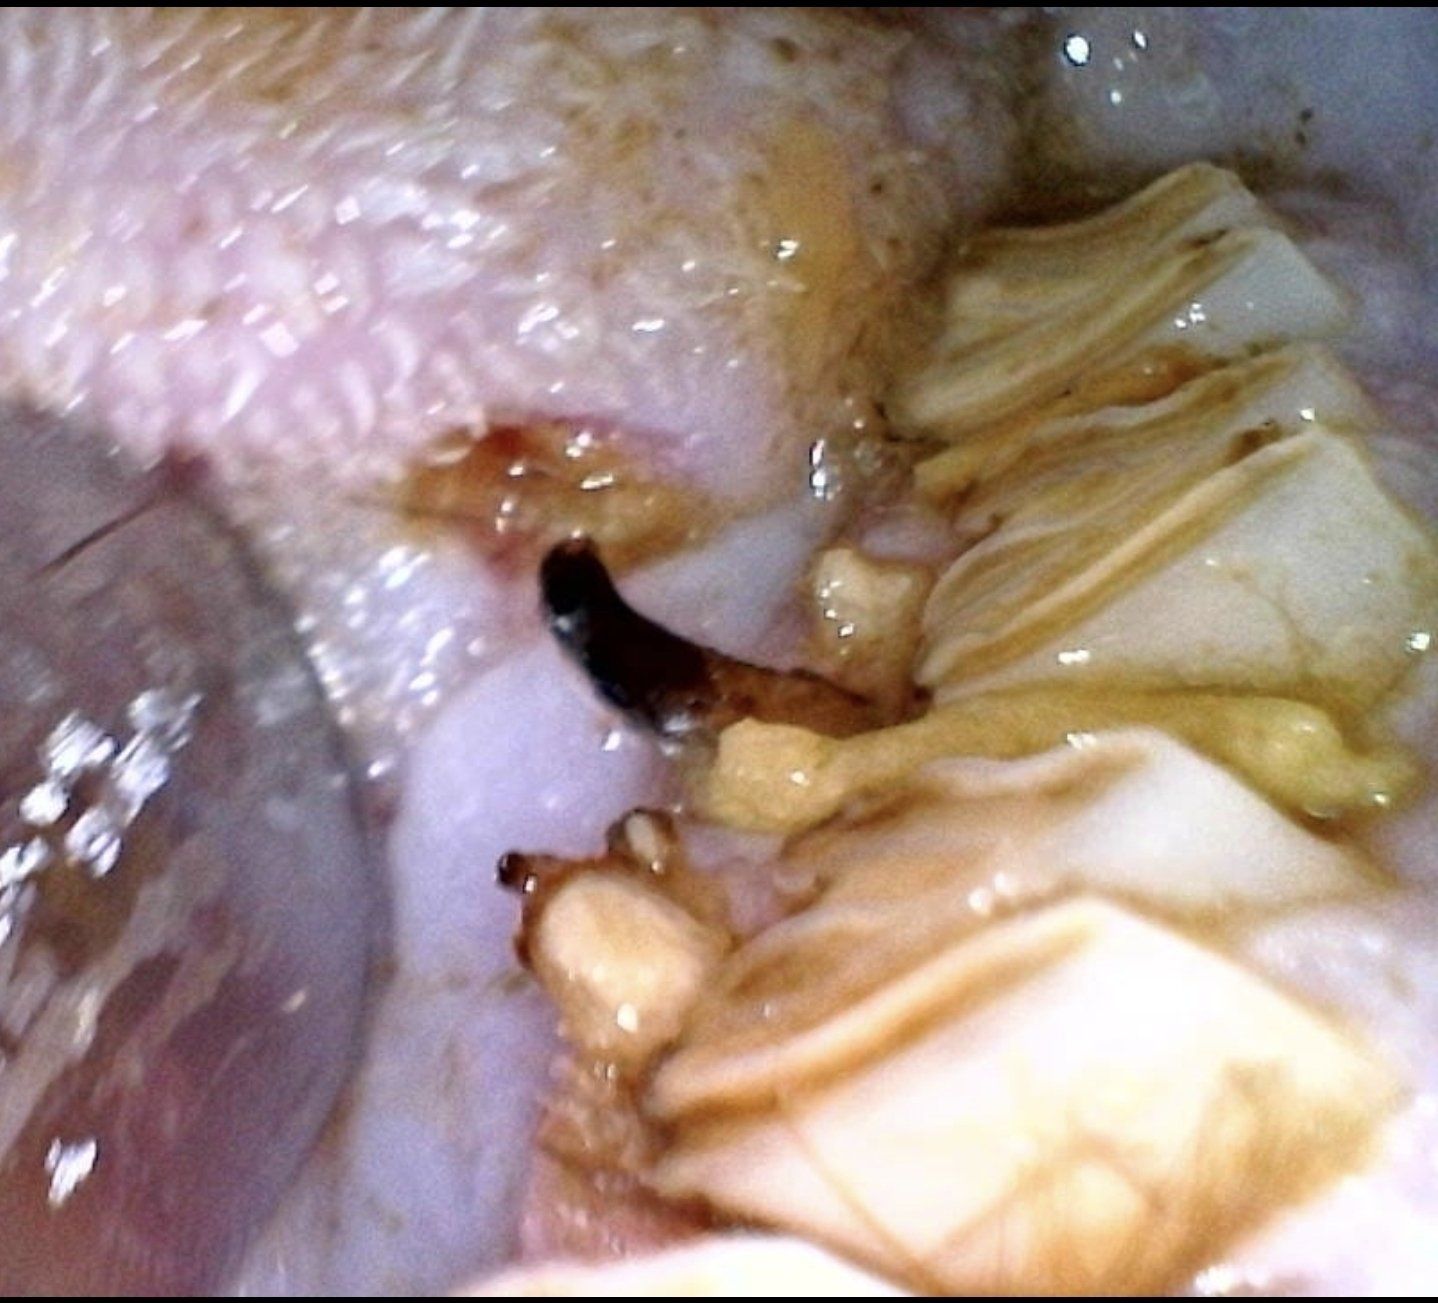

Abgegeben wurden 2 Urlaubs Schweinchen, die vor 6 Jahren bei einer "Züchterin" gekauft wurden. 6 Jahre lang wurde die Pflege der Tochter überlassen und 6 Jahre lang bekamen die Tiere keine ausreichende Pflege. Das Zahnproblem hatte man nicht bemerkt und der Fuß wurde irgendwann schon mal mit ein bisschen Salbe behandelt. Die Zahnbrücke hat schon in die Zunge geschnitten... Ein Wunder wie der arme Kerl noch fressen konnte.